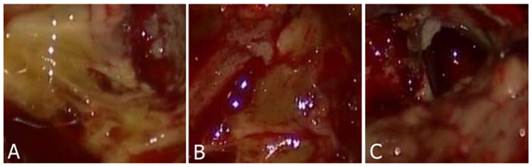

Three color degrees of staining were observed that were deep yellow, light yellow and negatively stained. Normal brain parenchyma remained unstained. Tumor stained with yellow was easily identified from the normal brain parenchyma (Fig. 1A-C). Most of the patients (n=9) within the study group (n=10) had tumors that were positively stained with fluorescein sodium. The case that did not have a positively stained tumor was subsequently identified to have a grade II glioma. Meanwhile, we reviewed pre-operative enhanced MRI and found that the edges of the tumor were not clearly enhanced.

A-B: Tumor tissue was stained by fluorescein sodium presenting deep to light yellow color. C: Normal parenchyma was not stained.